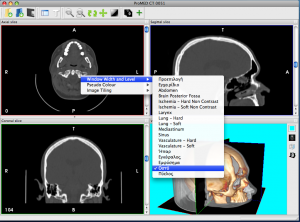

InVesalius is an image processing software dedicated to DICOM images (“.dcm” / “.DCM” extension) produced by imaging equipment (CT, MRI). It is fully compliant with the DICOM standard for image communication and image file formats. InVesalius is able to read 2D images and build 3D models of the region of interest.

InVesalius has been designed for navigation and visualization of multidimensional images: 2D viewer and 3D viewer and also for rapid prototyping anatomical structures. The 3D Viewer offers all modern rendering modes: Multipla

nar reconstruction (MPR), Surface Rendering, Volume Rendering and Maximum Intensity Projection (MIP). Surfaces created by InVesalius can be exported to OBJ, STL or other 3D files supported by Blender or other software. It is completely written in Python. Also, we only use free software tools in its development, including VTK (Visualization Toolkit), wxPython, GDCM (Grassroots DICOM), ITK (Insight Toolkit), NumPy, PIL (Python Imaging Library).